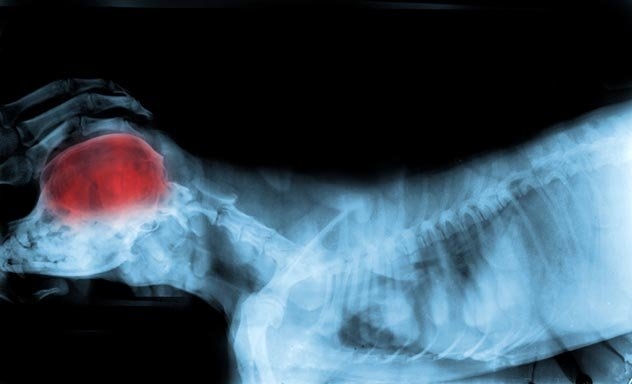

Мозок собак різних порід відрізняється

Мозок собаки змінюється в залежності від породи. Деякі з них призначені для полювання, а інші - для пошукових операції. Велика частина цієї поведінки виникла під впливом людини. Вчені довели, що селекція, яку ми використовували протягом багатьох років, щоб отримати бажану форму, колір або поведінку, також вплинула на роботу мозку собаки. Це означає, що собаки відрізняються не тільки за розміром, формою і кольором, але й за способом роботи їх мозку.